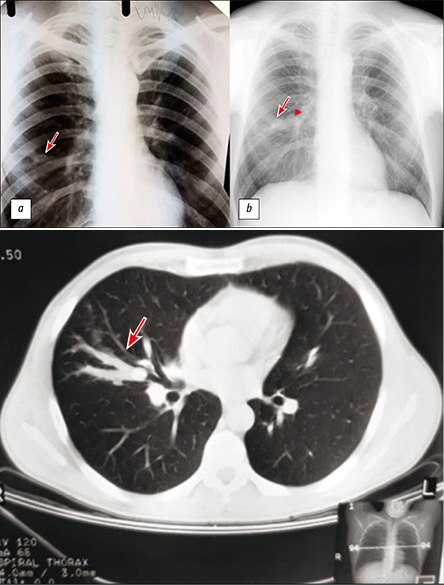

Длительный анамнез бронхоцеле, вызванный типичным карциноидом

Аннотация

В работе представлен клинический случай с длительным периодом наблюдения одиночного бронхоцеле (бронхогенной ретенционной кисты). При первоначальном комплексном обследовании, включающем такие исследования, как рентгенография, компьютерная томография органов грудной полости, фибробронхоскопия, иммунологические и бактериологические обследования на туберкулёз, данных за онкологическую и инфекционную природу изменений не выявлено. Изменения были расценены как последствия перенесённого неспецифического воспалительного процесса. Через 15 лет при плановом медицинском осмотре по данным рентгенографии органов грудной полости отмечено увеличение размеров бронхоцеле, а также появление округлого образования в медиальных отделах бронхоцеле. С помощью дополнительных методов исследования, таких как компьютерная томография органов грудной полости с внутривенным контрастированием, фибробронхоскопия с биопсией, установлено, что выявленное образование является типичным карциноидом.

Несмотря на то что бронхоцеле в большинстве случаев является доброкачественным изменением, из разнообразия причин, вызывающих его развитие, следует выделить обструкцию бронха новообразованием. Среди новообразований лёгкого типичный карциноид составляет всего 1–2%, характеризуется крайне медленным ростом и отсутствием специфичной клинической симптоматики. Несмотря на это, типичный карциноид относится к злокачественным нейроэндокринным образованиям I типа. В 10–15% случаев выявляются метастазы, преимущественно в медиастинальные лимфатические узлы, а также в печень, кости, реже в мягкие ткани.

Данное клиническое наблюдение говорит о том, что даже при отрицательных результатах первичного обследования локально расположенного бронхоцеле такие изменения требуют онкологической настороженности и периодических обследований в динамике.